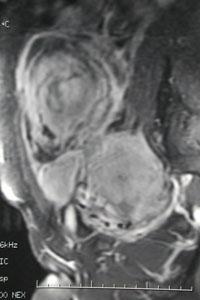

可能为子宫平滑肌肉瘤

2. 子宫恶性肿瘤:子宫肌肉瘤;卵巢癌;子宫内膜癌(绝经期后出血或不规则出血) 。重要的是你能否识别子宫恶性肿瘤。 子宫内膜癌